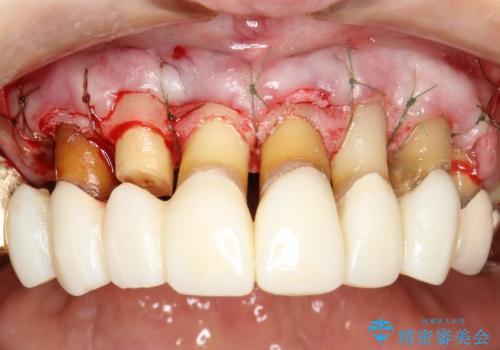

- 歯周外科・再根管治療後、クラウンを製作する。

- 外科手術のため、術後に痛みや腫れ、違和感を伴います

- 歯周組織再生治療は患者様の状態によって術後の経過が異なります(見た目が改善しない場合もあります)

- 根管治療により痛みや腫れがひかない事や、術後に痛みや腫れが生じる事、治療によるファイル破折やパーフォレーションなどの偶発症、術後の歯根破折を生じる可能性もあります